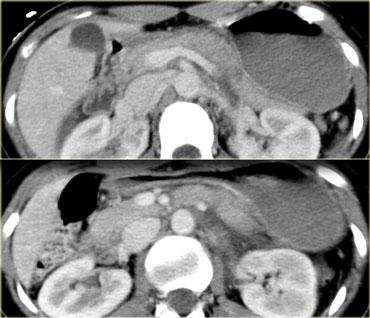

Trước tiên hãy quan sát các hình ảnh bên trái của bệnh nhân bị chấn thương gan.

Các dấu hiệu CT trong trường hợp này là gì?

Các dấu hiệu bao gồm:

- Mất tưới máu hoàn toàn thùy gan phải.

- Vùng ngấm thuốc cản quang (contrast blush) trong nhu mô gan, đồng thời lan ra ngoài bờ bên của gan.

- Tràn máu ổ bụng (Hemoperitoneum).

- Một vùng ngấm thuốc cản quang thứ hai ở mức thấp hơn.

- Tụ máu dưới bao gan lớn hơn 10 cm (tức là tổn thương độ 4)

- Vùng ngấm thuốc cản quang (contrast blush) (mũi tên)

- Không có tràn máu ổ bụng kèm theo

Vì vậy, mặc dù có thoát thuốc cản quang, bệnh nhân này sẽ được điều trị bảo tồn (không phẫu thuật) và có thể có tiên lượng tốt, do không có chảy máu vào khoang phúc mạc.

Thoát thuốc cản quang có ý nghĩa đặc biệt quan trọng, nhất là khi kết hợp với tràn máu ổ bụng.